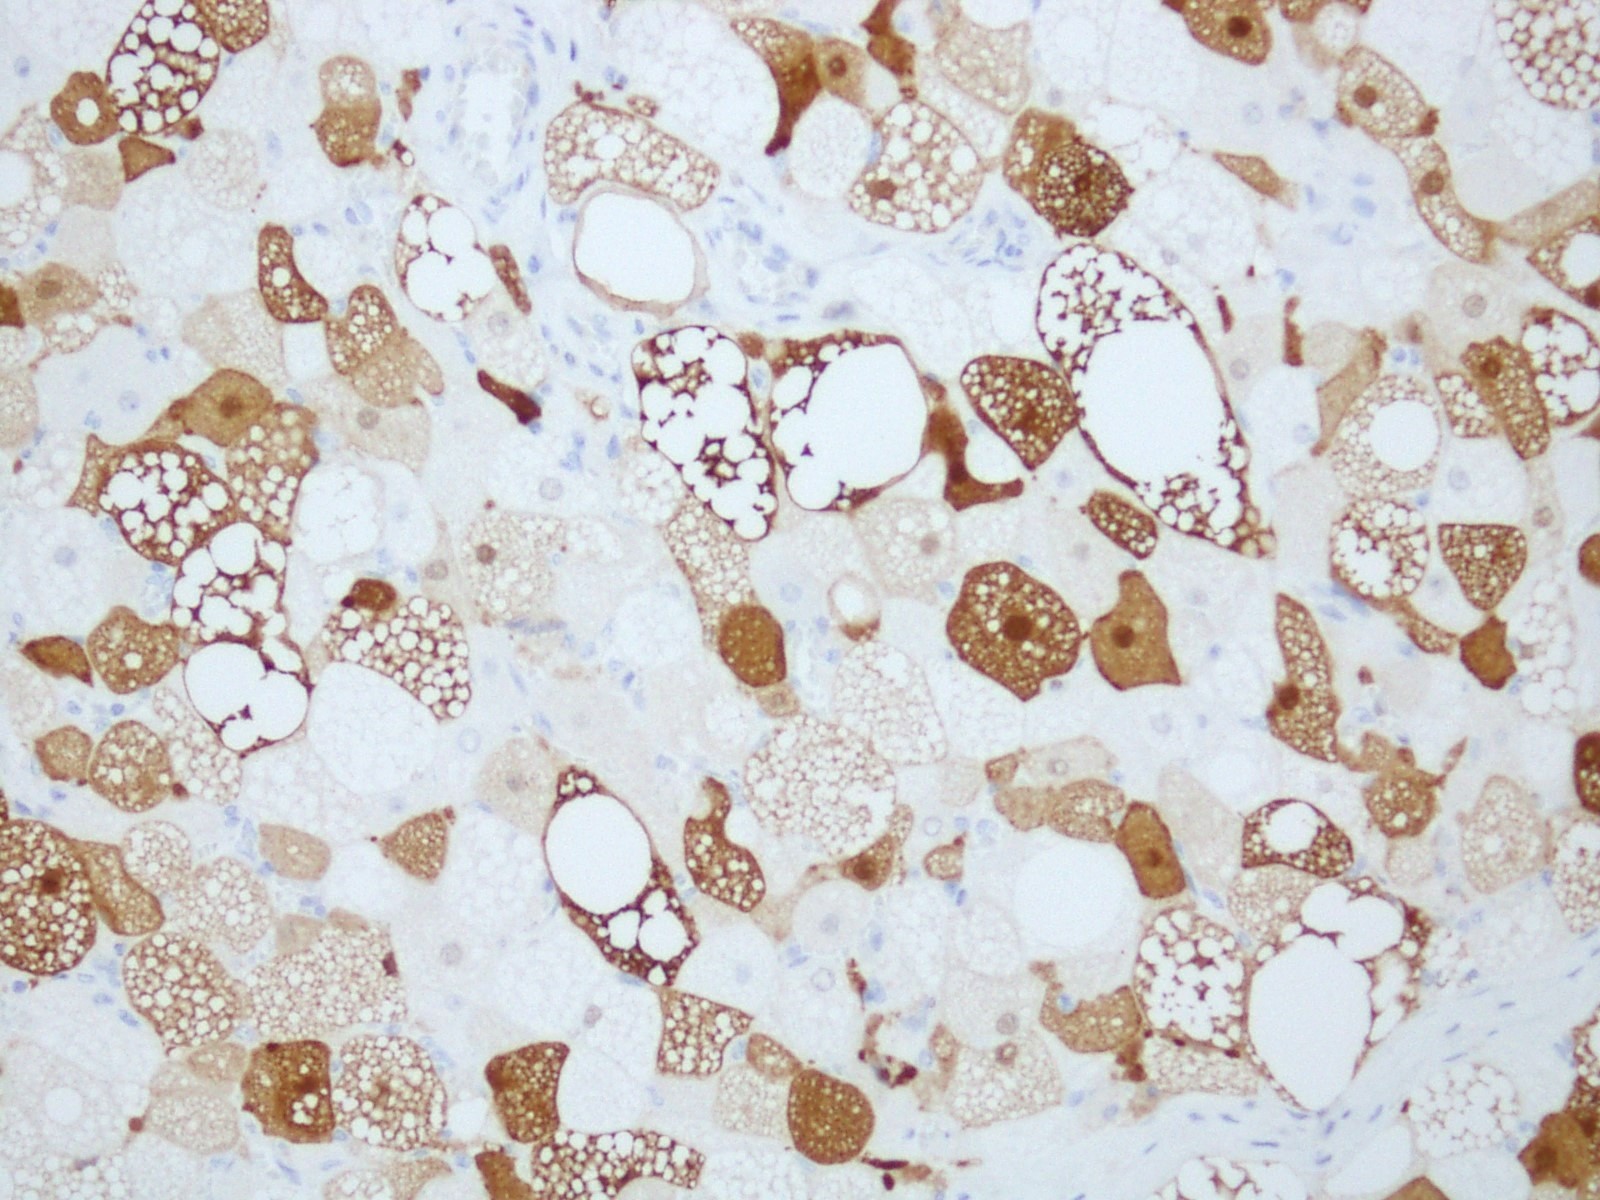

Microscopic (histologic) images

Positive stains

- S100 (Skeletal Radiol 2022;51:1325, J Pathol Transl Med 2017;51:499)

- Ki67 absent to very low (Case Rep Oncol 2017;10:438)

- CD34 (can be positive in spindle cell component) (BMC Surg 2021;21:30)

- Brown fat cells in hibernoma stain strongly with the anti-UCP1 antibody (Clin Sarcoma Res 2019;9:8)

- Periodic acid-Schiff with diastase digestion (PASD) reveals PAS positive, diastase resistant cytoplasmic granules (J Clin Diagn Res 2017;11:ED01)

- CD10 (Hum Pathol 2021;110:12)